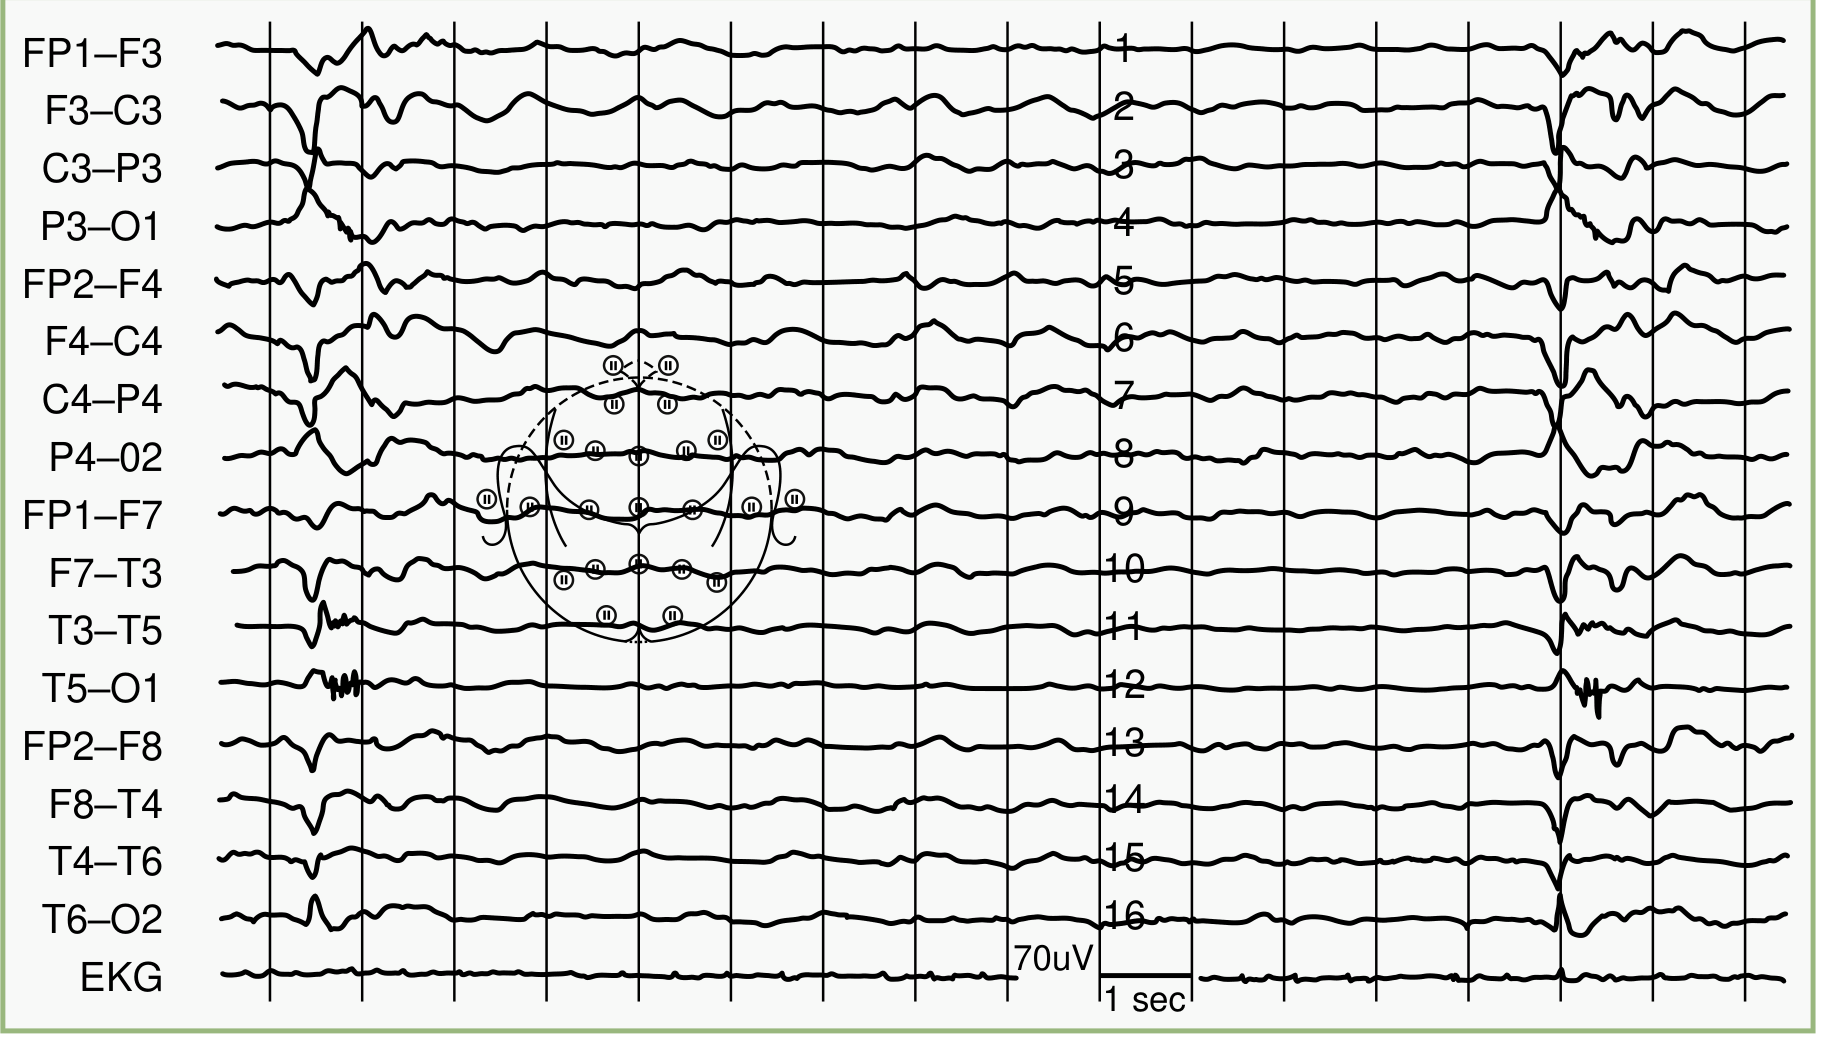

EEG

Pathognomonic pattern: Periodic bursts of 2–3 Hz high-voltage sharp/slow waves occurring at regular intervals of every 3–8 seconds (up to 4–14 seconds apart), against a background of attenuated ("flat") activity. The bursts may last up to 3 seconds.

SSPE EEG — Periodic generalized slow-wave complexes occurring approximately every 12 seconds (Bradley & Daroff's Neurology)

Fig. 78.9 — EEG of a 23-year-old with SSPE showing characteristic periodic slow-wave complexes. (Bradley & Daroff's Neurology in Clinical Practice)